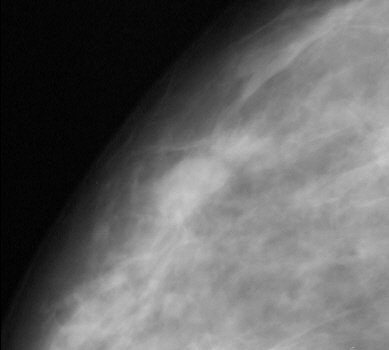

| Same patient. A digital magnification of the image above. Cancers in both left and right breasts were marked by CAD system. Butler SA, Gabbay RJ, Kass DA, Siedler DE, O'Shaughnessy KF, Castellino RA, "Computer-Aided Detection in Diagnostic Mammography: Detection of Clinically Unsuspected Cancers," (AJR 2004; 183: 1511-1515). |